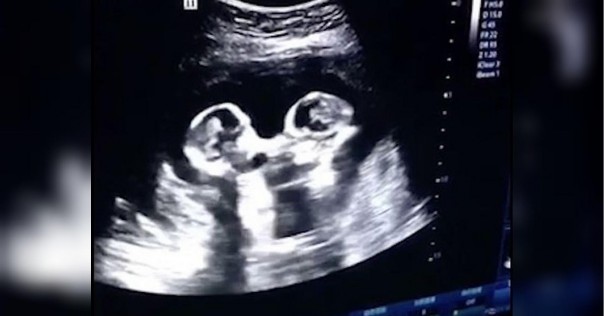

Согласно первому глобальному обзору, опубликованному в Human Reproduction, одном из ведущих мировых журналов по репродуктивной медицине, на данный момент в мире у людей рождается больше дизиготных, или разнояйцевых близнецов, чем когда-либо прежде.

С 1980-х годов количество двойняшек увеличилось на треть — с 9 до 12 на 1000 родов, а это означает, что ежегодно во всем мире рождается около 1,6 миллиона двойняшек, и близнецом является каждый 42 рожденный ребенок.